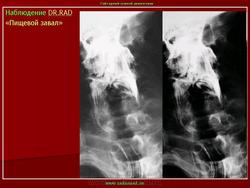

И.Бондаренко wrote:

Интересно, а, что такое "пищевой завал"?

"Пищевой завал" чаще наблюдается у лиц преклонного возраста, по статистике чаще у мужчин. В результате снижения тонуса пищеварительной трубки крупный пищевой кусок, чаще - мясо, просто застревает и обтурирует просвет пищеварительной трубки, чаще на уровне глотки, верхней части пищевода, но на много чаще на уровне 1 физиологического сужения - "рот Килиана".